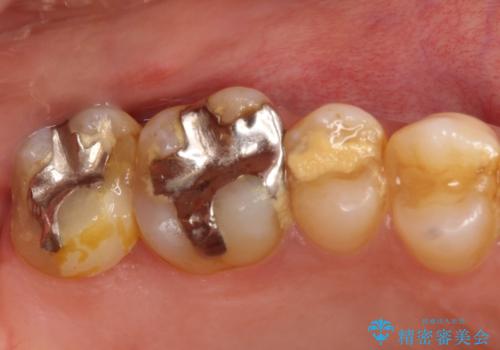

目立つ銀歯と欠けてしまった詰め物 オールセラミッククラウンでの補綴治療

不快感の強い奥歯 オールセラミッククラウンでのむし歯治療